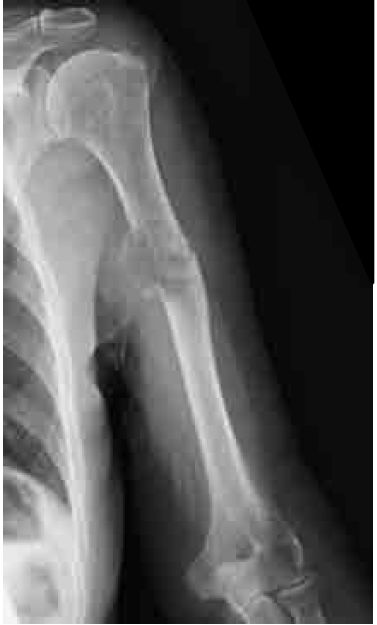

■ 問41

74 歳の女性.左手をついて立ち上がろうとした際に,左上腕が変形し激痛が生じたため受診した.左上腕骨単純X 線正面像を示す.その後検査で腎癌が発見された.病状の評価と今後の治療方針について正しいのはどれか.

a 手術適応にはならない.

b 移動能力には影響がない.

c 骨軟部腫瘍専門医でなければ対応は困難である.

d がん治療の継続のために移動機能の維持が重要である.

e 原発病変の治療に先行して上腕骨の治療を開始することはない.

正解:d